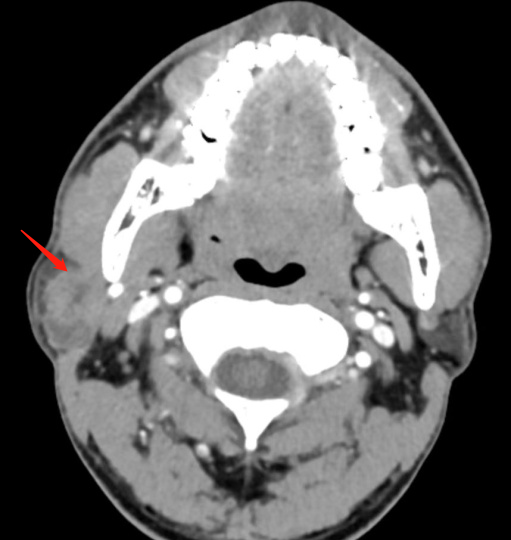

收治入院后,刘蓉蓉主任对张先生进行了详细的查体,并做了腮腺 CT 检查。CT 提示:右侧腮腺的深叶肿瘤。大小约 3x2 cm。

仔细询问病史并阅读 CT 片后,刘蓉蓉主任指出其肿瘤恶性可能性较大,且瘤体较大,面神经部分被包绕。手术难度高,但也必须尽快手术。